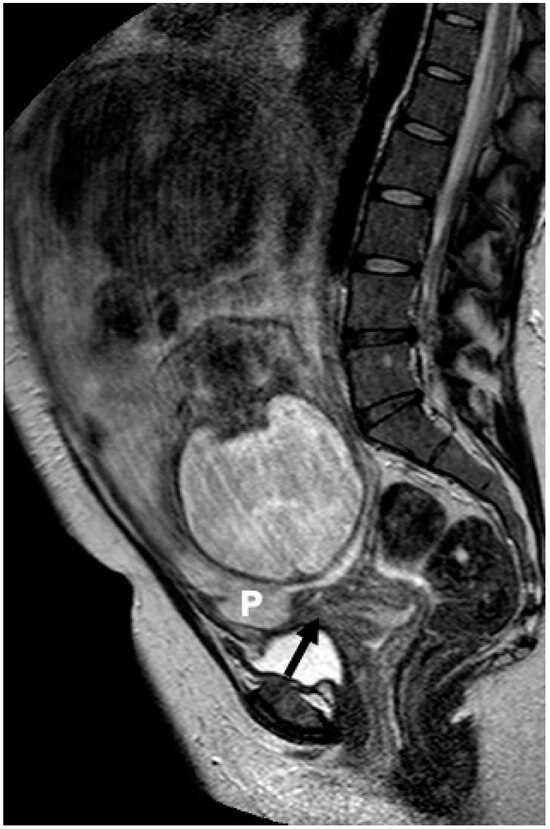

2.2. MRI Protocol

2.3. Image Interpretation